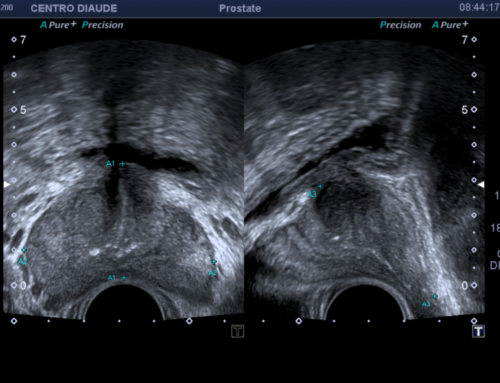

La ecografía testicular es una técnica de imagenología que utiliza ondas de sonido de alta frecuencia para obtener imágenes detalladas de los testículos, el epidídimo y otras estructuras del área escrotal.

- El especialista desliza un transductor de ultrasonido sobre el área escrotal.

- Las ondas de sonido emiten imágenes detalladas en una pantalla.